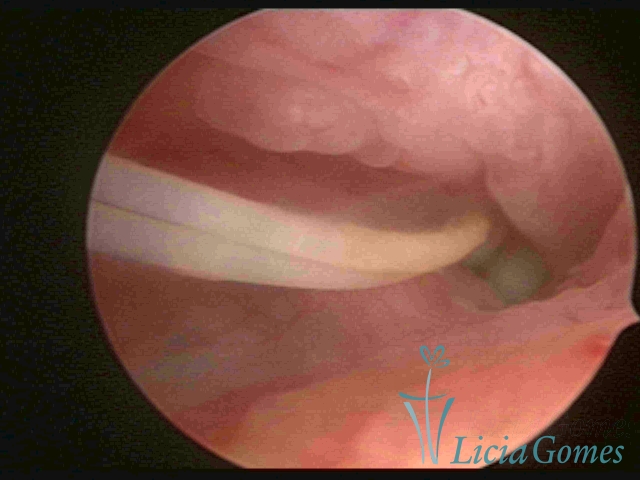

IUD distal extremity